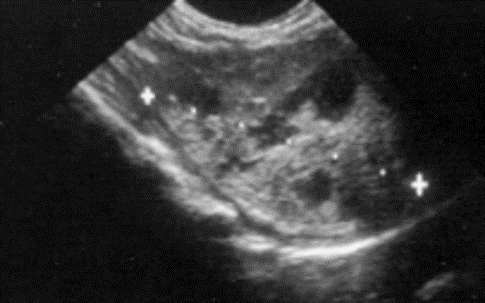

Which best describes US signs?

What is the likely diagnosis?

Heterogenous

Irregular shapes

Poorly marginated

Diagnosis:

Neoplasia – so much worse than others